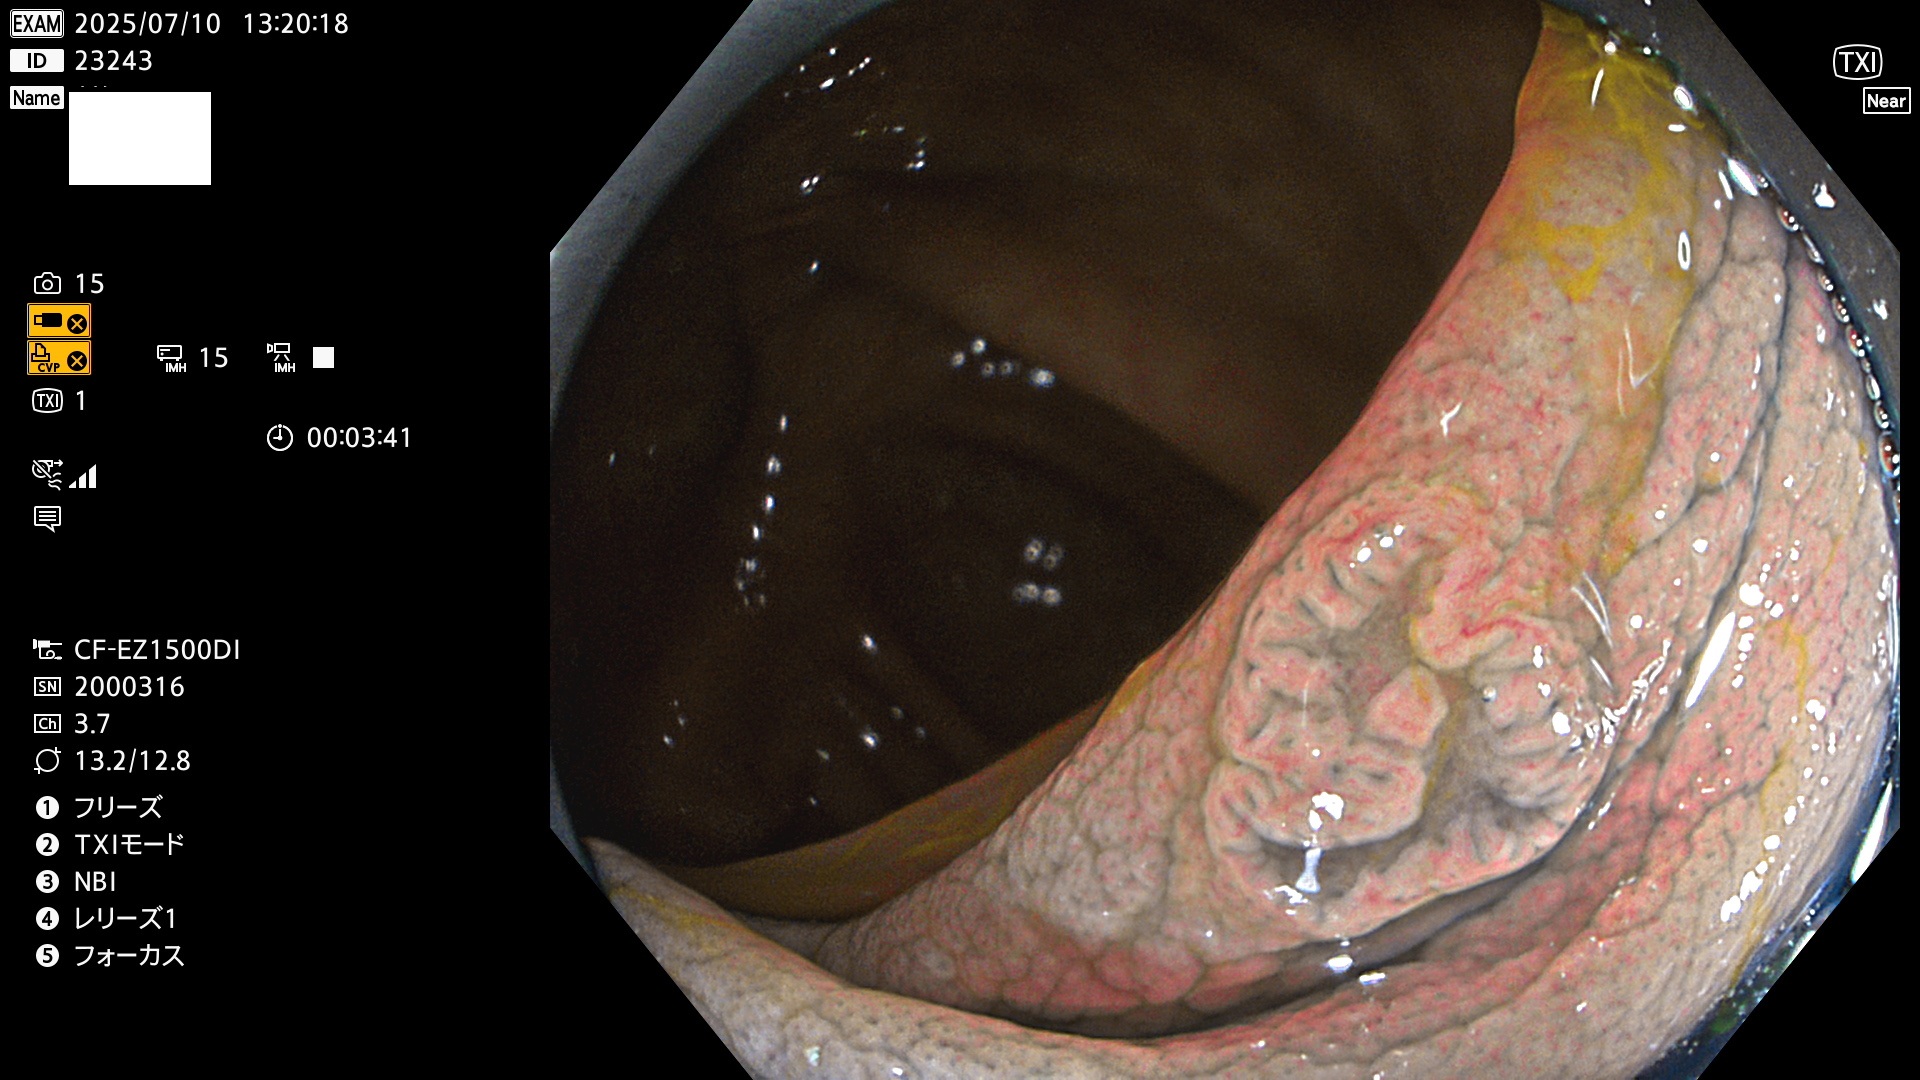

2025年7月10日〜7月13日の4日間(40件)15個 (Uc_ADR=15/40=38%)